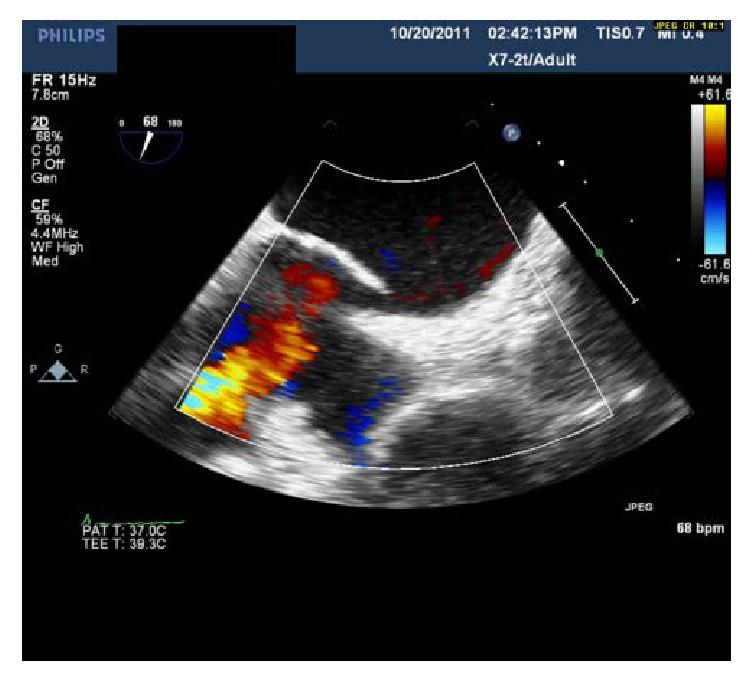

伴有半膈麻痹的有症状卵圆孔未闭

Symptomatic Patent Foramen Ovale with Hemidiaphragm Paralysis.

Dyspnea accounts for more than one-fourth of the hospital admissions from Emergency Department. Chronic conditions such as Chronic Obstructive Pulmonary Disease, Congestive Heart Failure, and Asthma are being common etiologies. Less common etiologies include conditions such as valvular heart disease, pulmonary embolism, and right-to-left shunt (RLS) from patent foramen ovale (PFO). PFO is present in estimated 20-30% of the population, mostly a benign condition. RLS via PFO usually occurs when right atrium pressure exceeds left atrium pressure. RLS can also occur in absence of higher right atrium pressure. We report one such case that highlights the importance of high clinical suspicion, thorough evaluation, and percutaneous closure of the PFO leading to significant improvement in the symptoms.

摘要

呼吸困难占急诊科住院患者的四分之一以上。慢性阻塞性肺疾病、充血性心力衰竭和哮喘等慢性疾病是常见病因。较少见的病因包括瓣膜性心脏病、肺栓塞以及卵圆孔未闭(PFO)导致的右向左分流(RLS)。估计20%-30%的人群存在PFO,大多为良性情况。通过PFO的RLS通常在右心房压力超过左心房压力时发生。在没有较高右心房压力的情况下也可能发生RLS。我们报告了这样一个病例,强调了高度临床怀疑、全面评估以及经皮闭合PFO对显著改善症状的重要性。